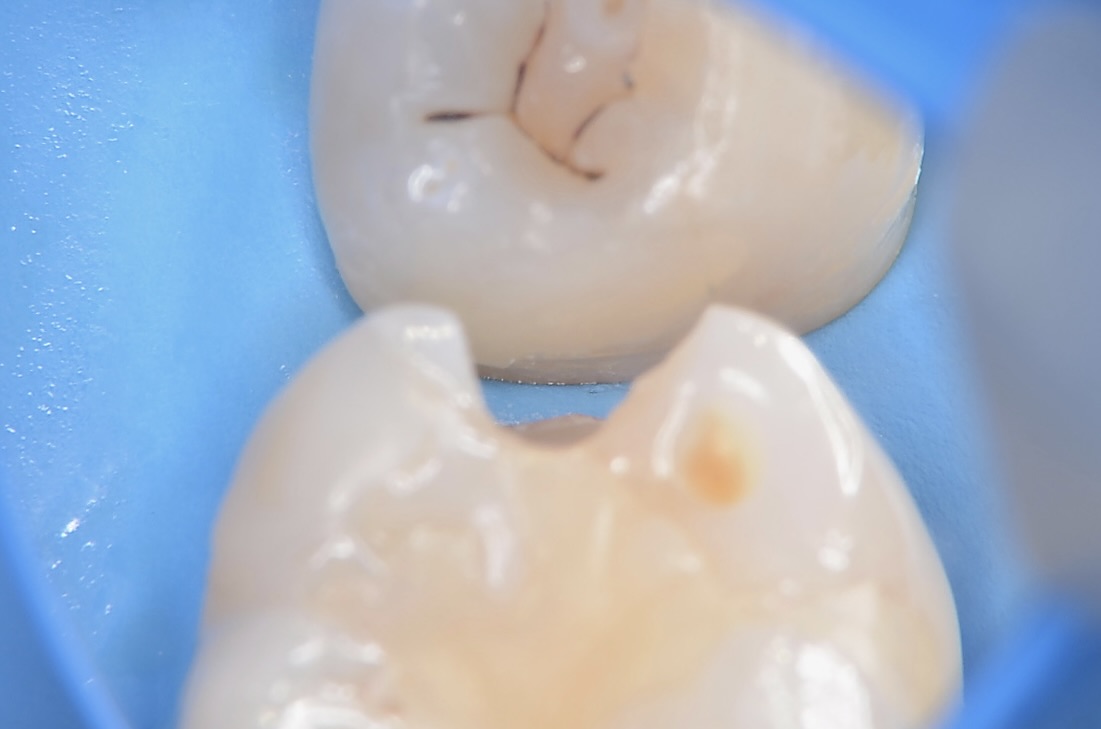

少し歯を削ったところ

齲蝕検知液で染めると虫歯が青く染まります。 -

咬合面観

6番近心の虫歯を取り除いたところです。 -